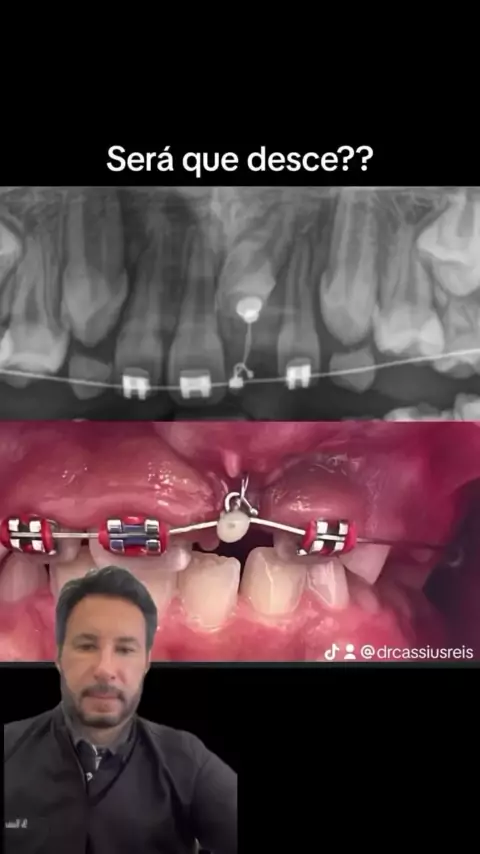

Traçao ortodôntica em paciente jovem (8 anos), mesmo com chances reduzidas é preciso tentar!! caso contrário, se o dente nao descer e for necessário extrair, o paciente só poderá fazer implante para reposição por volta dos 18 anos quando termina o crescimento dos ossos da face. Imaginem o paciente ter que conviver com um provisório (removivel)dos 8 aos 18 anos 😔.Vamos torcer para que a movimentação ocorra e de tudo certo!!🙏 #ortodontia